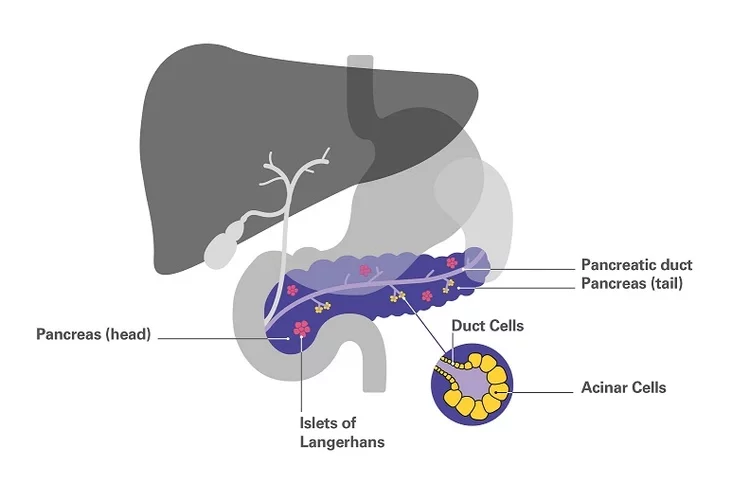

Мікрабіёлагам і анколагам універсітэта ўдалося выявіць спецыялізаваны бялок, які прысутнічае ў ракавых клетках адэнакарцыномы пратокаў падстраўнікавай залозы чалавека (PDAC) і наўпрост уплывае на рост пухліны. Падчас вывучэння гэтага бялку навукоўцы выявілі, што тэрапія мадыфікаванай версіяй супрацьзапаленчага прэпарата суліндак можа блакаваць бялок і спыняць рост новаўтварэнняў.

Вядучы аўтар даследавання, прафесар Марка Фаласка адзначыў, што цяпер існуе вельмі абмежаваная колькасць метадаў лячэння для людзей з агрэсіўным тыпам раку падстраўнікавай залозы і ўсе яны даюць не дужа значныя вынікі. «PDAC - вельмі агрэсіўнае захворванне, і, як правіла, пацыенты з такім дыягназам маюць не вельмі аптымістычны прагноз, бо сярэдні тэрмін жыцця пасля тэрапіі, у якую ўваходзіць хірургічнае ўмяшанне, як правіла, не перавышае пяці гадоў, што і робіць яго чацвёртай найбольш пашыранай прычынай смерці ад раку ў заходнім свеце», - сказаў прафесар Фаласка.

Падчас выпрабаванняў на мышах навукоўцы змаглі вызначыць, што блакаваньне бялку з дапамогай мадыфікаванага суліндака значна памяншае пашырэнне PDAC і запавольвае рост пухліны. Прафесар Фаласка растлумачыў, што атрыманыя вынікі патэнцыйна маюць каласальнае значэнне для лячэння раку падстраўнікавай залозы, бо бялок, які вывучаецца ў гэтым даследаванні, таксама выклікае рэзістэнтнасць да наяўных у цяперашні час хіміятэрапеўтычных прэпаратаў супраць раку.